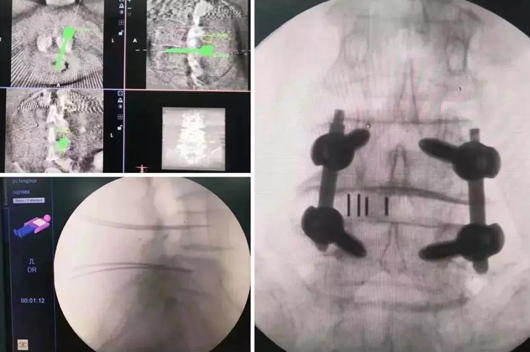

10月12日至14日,,,,,,刘新宇教授团队划分在骨科机械人辅助下完成MIS-TLIF手术、内镜下椎间融合内牢靠术(PE-TLIF)以及1例僵硬成人侧后凸畸形伴有椎板缺失和重度骨质松散的内牢靠手术。。。。。手术时,,,,,,首先对患者举行三维影像扫描,,,,,,图像被同步传输至天玑? 骨科手术机械人系统。。。。。医生在盘算机导航系统屏幕上设计好钉道,,,,,,天玑? 的机械臂将手术工具准确定位到手术位置,,,,,,套筒指向目的钉道的进钉点,,,,,,沿天玑? 套筒钻入经皮椎弓根螺钉导针,,,,,,术后复查证实螺钉被精准的置入到术前妄想的位置,,,,,,体现机械人在重大的脊柱畸形手术的优势。。。。。所有患者恢复优异,,,,,,手术清静性有了更好包管。。。。。

▲ 天玑? 辅助完成MIS-TLIF手术

▲ 天玑? 辅助内镜下椎间融合牢靠术(PE-TLIF)

▲ 天玑? 辅助脊柱侧后凸畸形手术

10月15日,,,,,,脊柱外科(骨肿瘤偏向)李建民教授团队也不甘示弱,,,,,,由李振峰教授主刀,,,,,,在天玑? 的辅助下完成了股骨转子位置肿瘤挖除后骨盆外架的装置牢靠,,,,,,骨盆外架装置时,,,,,,螺钉要求间距等宽,,,,,,徒手很难一次性完成植入,,,,,,有了天玑? 的助力,,,,,,指哪打哪。。。。。